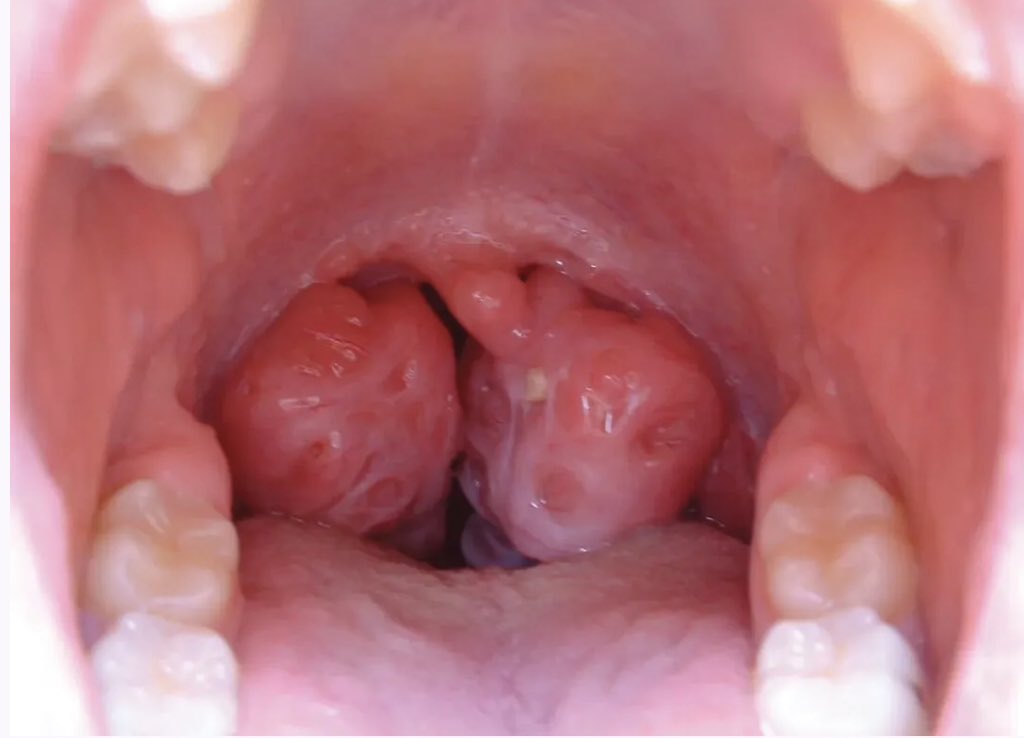

kissing tonsils 💋💋

What is the Diagnosis?